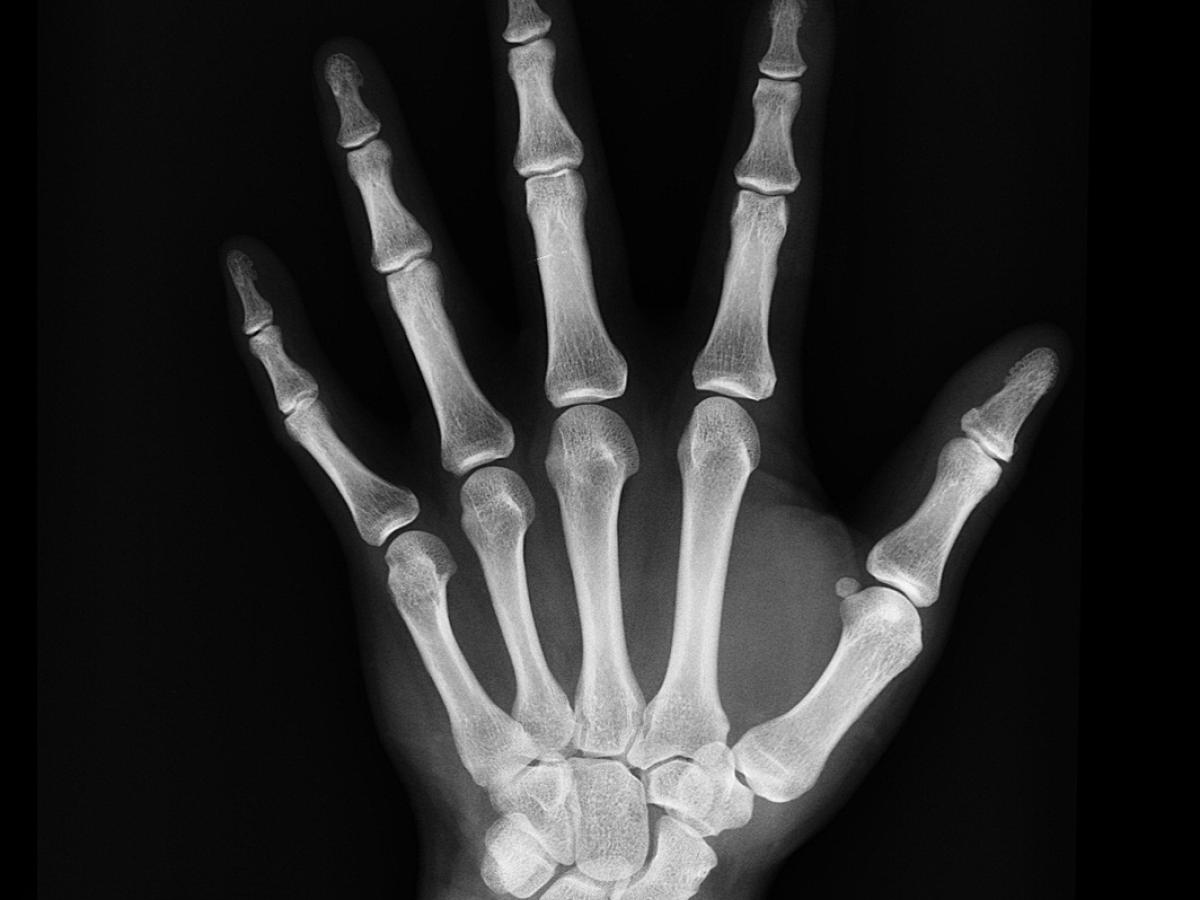

La Fundación Internacional de Osteoporosis estima que una persona sufre una fractura por osteoporosis cada 3 segundos en el mundo. La Asociación Colombiana de Osteoporosis y Metabolismo Mineral ACOMM, hace un llamado a niños, jóvenes y adultos a adoptar hábitos de vida saludables y especialmente a las mujeres en etapa de menopausia y adultos mayores al diagnóstico temprano, estas dos actividades crearan un ahorro saludable para favorecer la salud ósea. En el programa Contacto Directo el doctor Edgar Eduardo Castro Médico especialista en medicina interna y geriatría y Coordinador del programa de fracturas del SES Hospital Universitario de Caldas entregó detalles de la manera como se debe tratar y prevenir esta enfermedad.